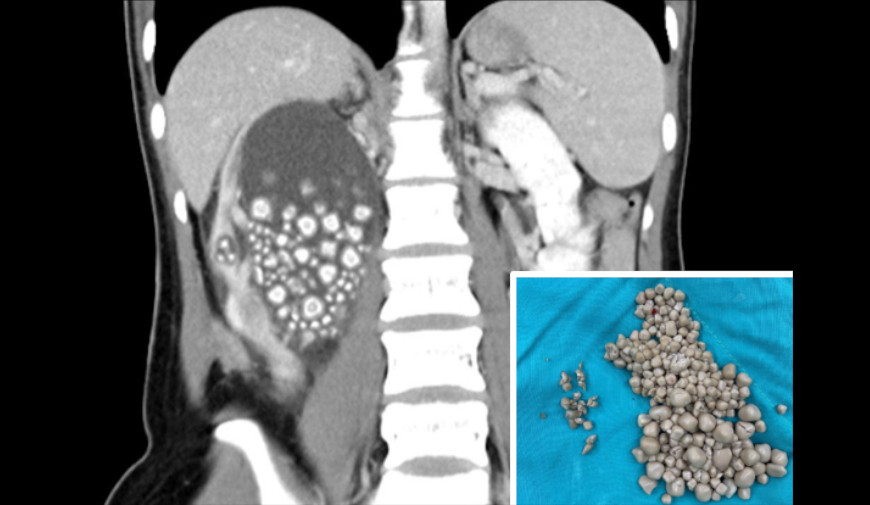

Pictures of different types of kidney stones

From edmm.jp

水の代わりにタピオカミルクティーばかり飲んでいた台湾人女性の腎臓から結石が300個以上摘出される! edamame. Edamame Kidney Stones Eating five to nine servings of vegetables and fruits every day can help reduce your risk of developing all kinds of kidney stones. This article will discuss the potential benefits and risks of edamame for those with kidney disease, as well as tips on how to safely incorporate it into their diet. Here is the good stuff! Low oxalate diets. Edamame Kidney Stones.